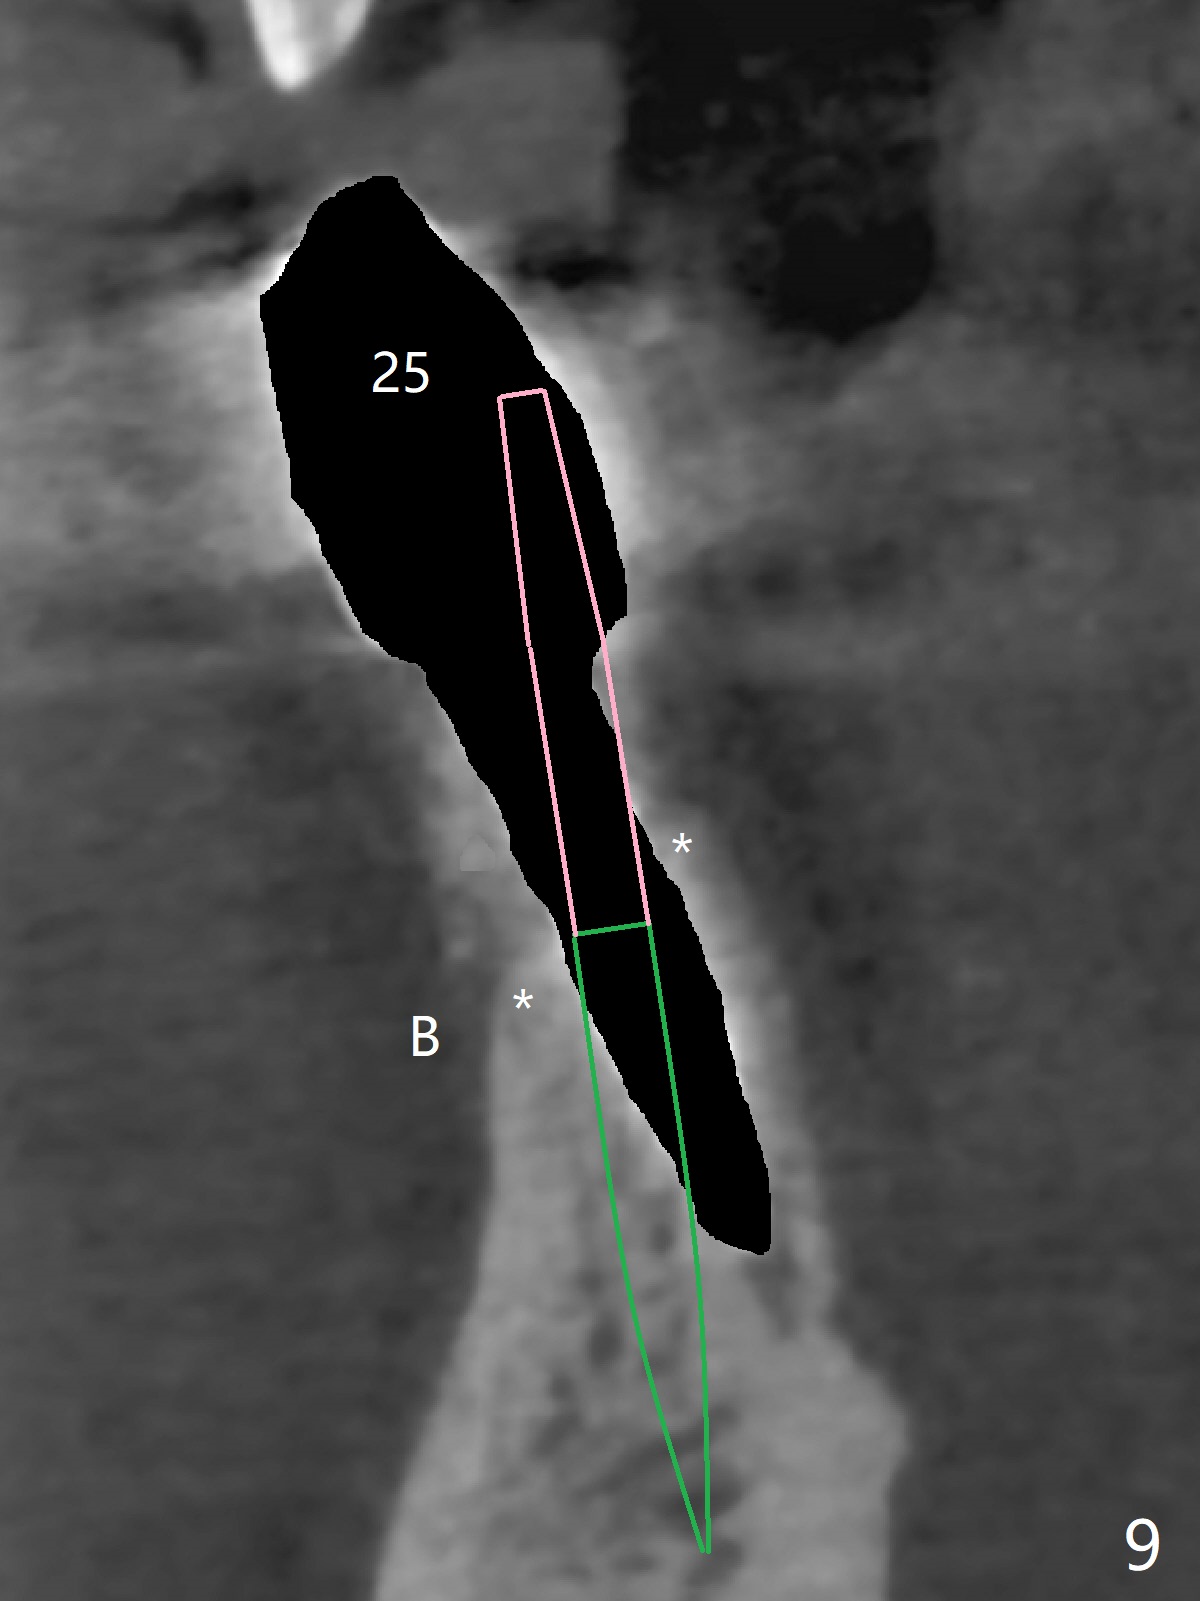

The fenetration found buccal to #25 two months post cementation persists, although asymptomatic, 4 months post cementation. Blood is drawn for PRF. In fact the implants at #24 and 25 are exposed buccal; there is limited amount of the buccal bone (Fig.1 *). After granulation tissue removal, Titanium brush is used to clean the implant threads. Allograft and Osteogen are mixed with PRF liquid to form gel, which is placed over the exposed implant threads. The bone graft is covered with a piece of PRF membrane and a piece of collagen membrane (Fig.2 C). Immediately postop PA (Fig.3) and CBCT (Fig.4) show that the implants have sufficient clearance between them. The implant thread exposure is most likely due to failure to place the implants deep enough and the implants are slightly large relative to the ridge (Fig.5-8). If the bone graft does not heal, new type of 1-piece implants (Fig.9,10 (green) smaller in diameter, 2 or 2.5 mm ) with longer abutment (pink) will be placed subcrestal buccal with guide.